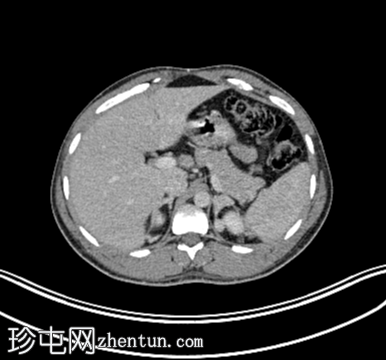

轴位增强CT

10.png